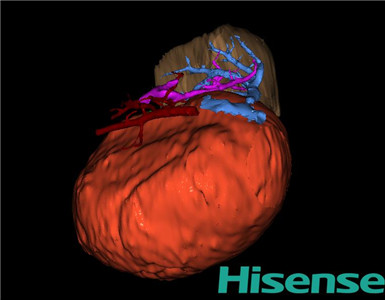

术前三维重建及手术方案设计:

将0.625mm双源薄层CT资料的静脉期和动脉期Dicom格式文件导入海信CAS系统。

通过调节窗宽窗位调整CT序号,对肝实质,胆囊,下腔静脉,肿瘤,肝动脉、门静脉及肝静脉等进行三维重建;系统自动计算肝脏体积。

模拟手术操作,自动计算切除肝体积、肿瘤体积、剩余功能性肝体积。

肝脏体积为218.1ml,肿瘤体积为1570ml,肿瘤体积为肝脏体积的7.2倍,通过比对1-3月正常肝脏体积为174.85±58.11ml,通过术前模拟手术,精准判断切除后剩余肝脏体积能耐受,避免肝衰竭发生。

术前三维重建:

重建图片